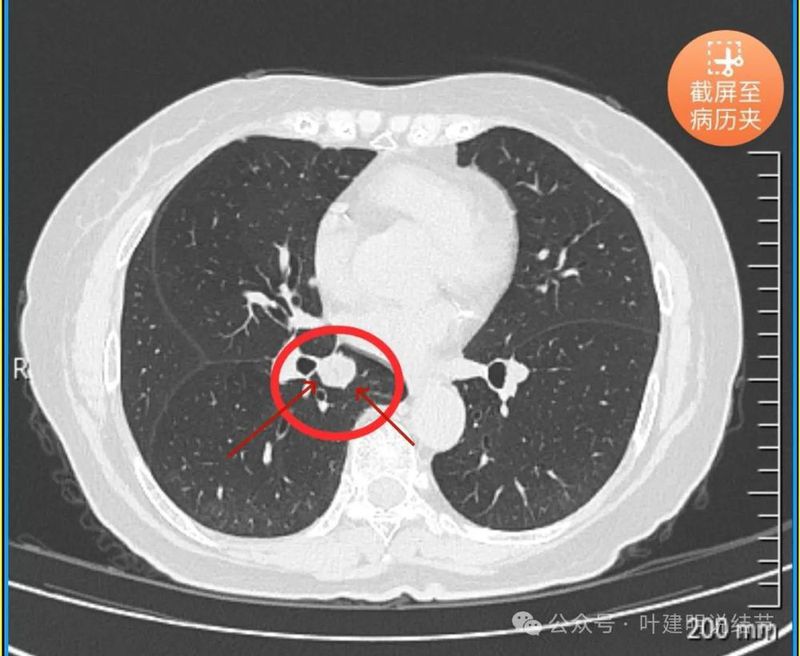

先看患者提供的2024年2月份的CT影像:

病灶出现,在右下叶支气管旁边,轮廓清楚,此层似磨玻璃密度。

表面似分叶状,密度不纯,邻近血管略有弯曲向病灶。

实性密度,边缘光滑,与背段支气管亚段贴着。